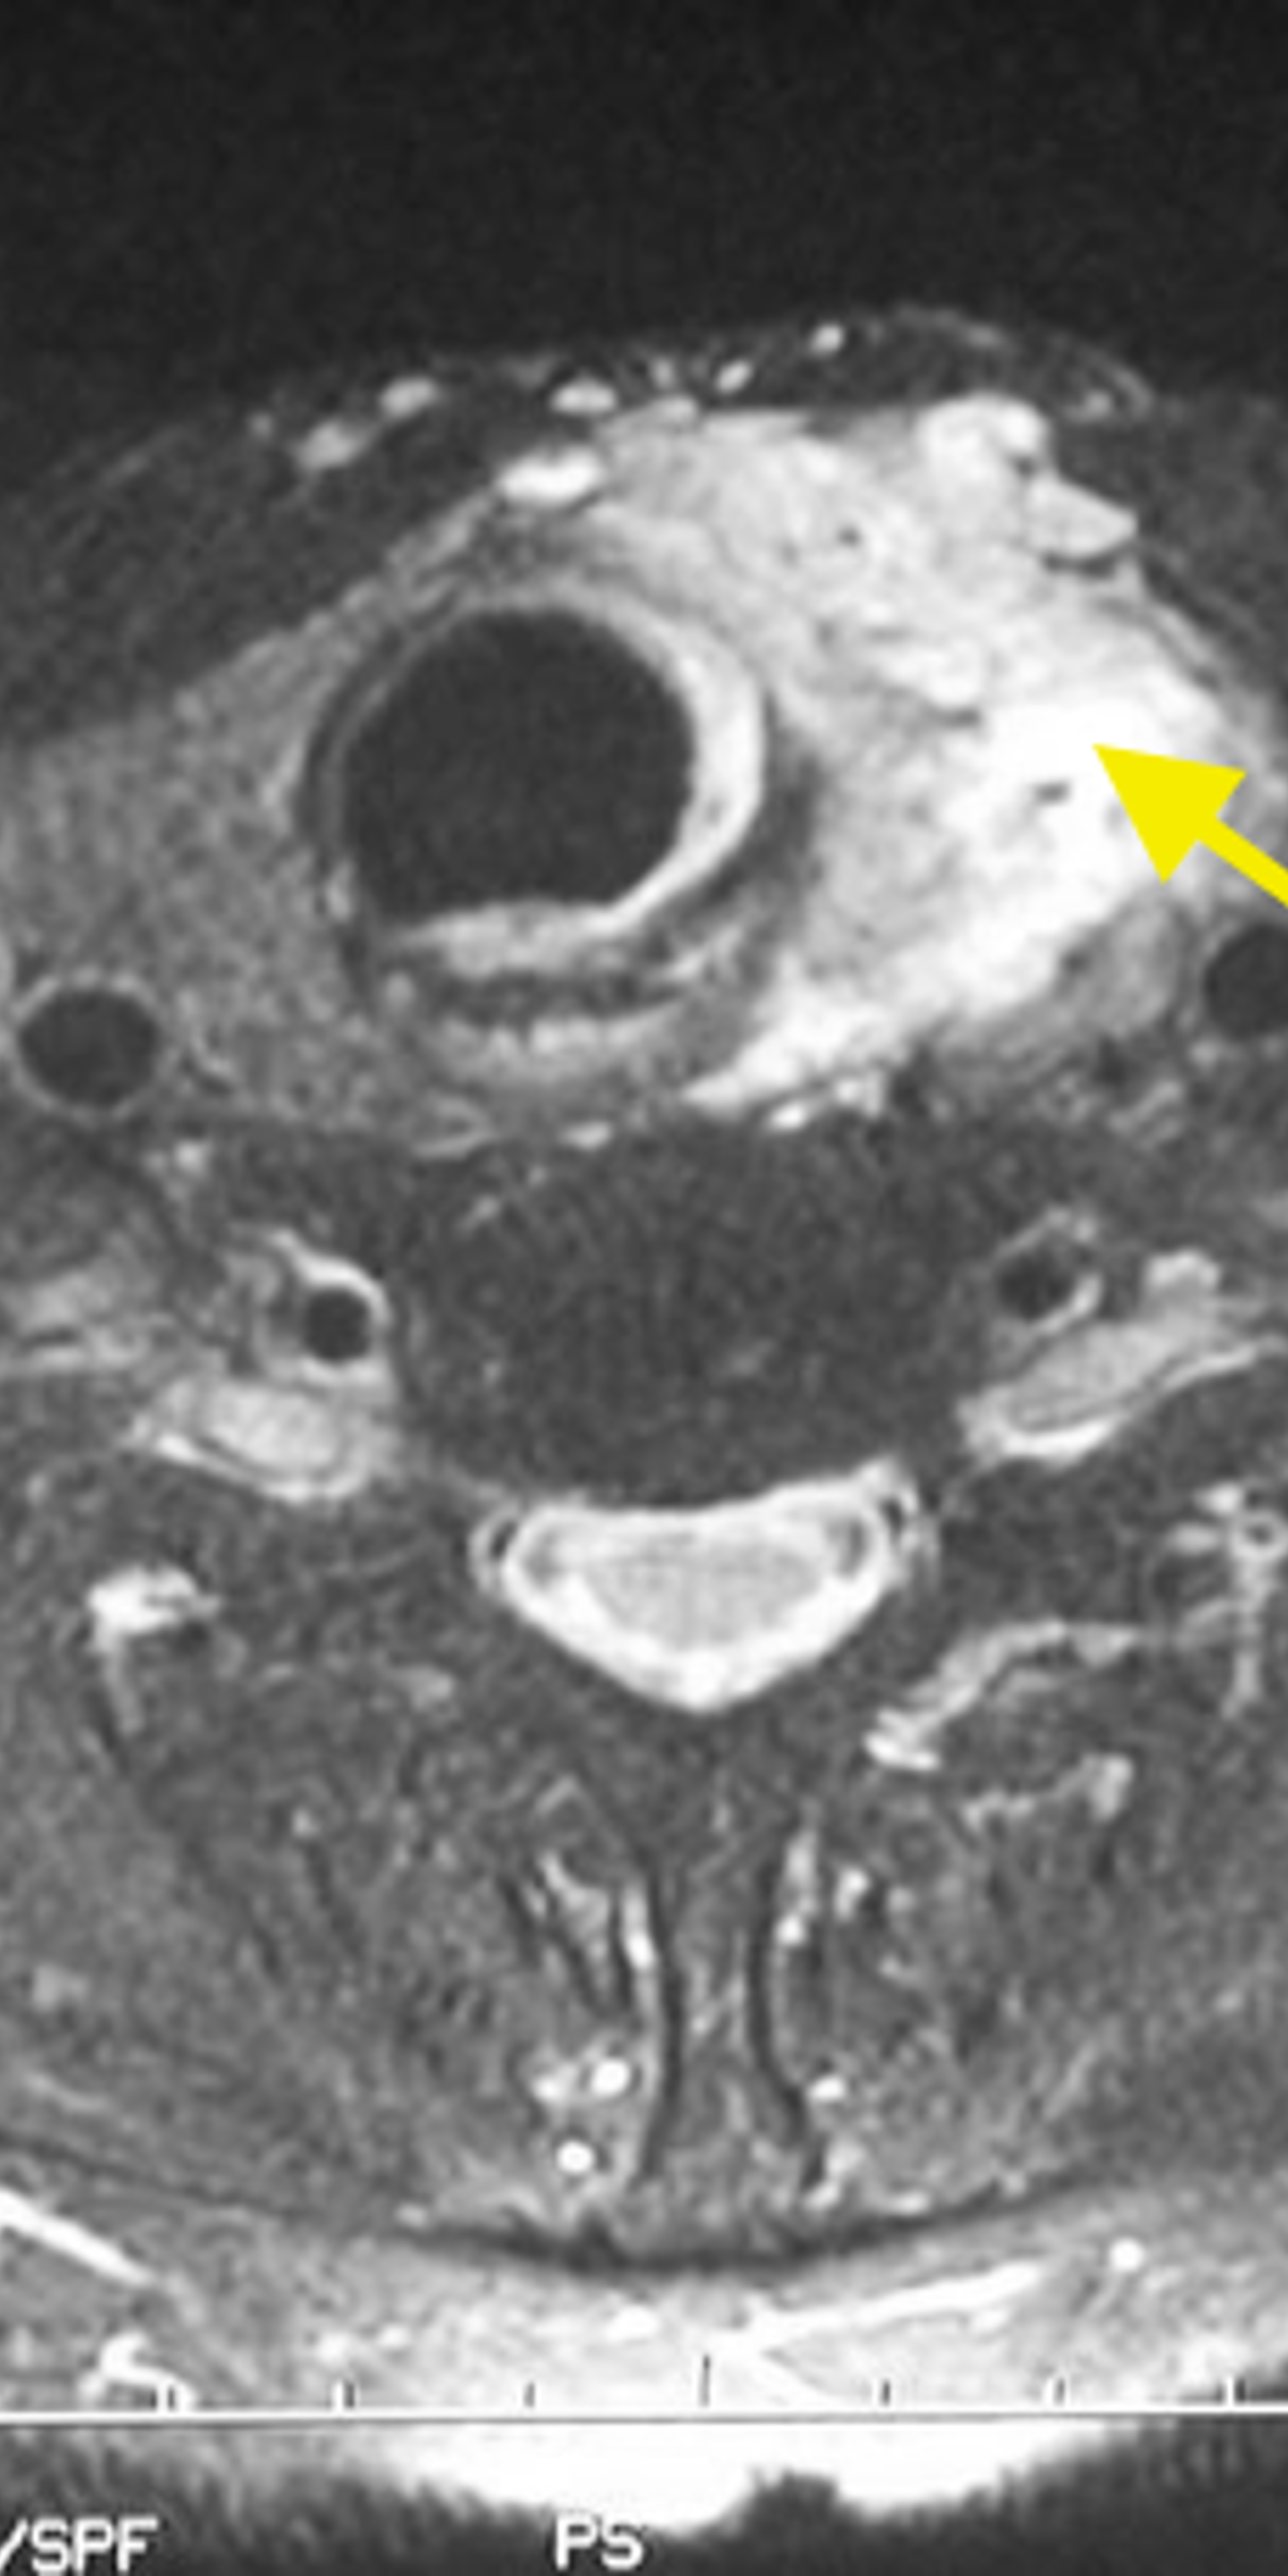

A CT Scan

CAT or CT (computed tomography) scans use advanced X-rays to give your physician a better view of your thyroid. It displays the location and size of a potentially cancerous lump, as well as informs your doctor if cancer has spread to other parts of your body.